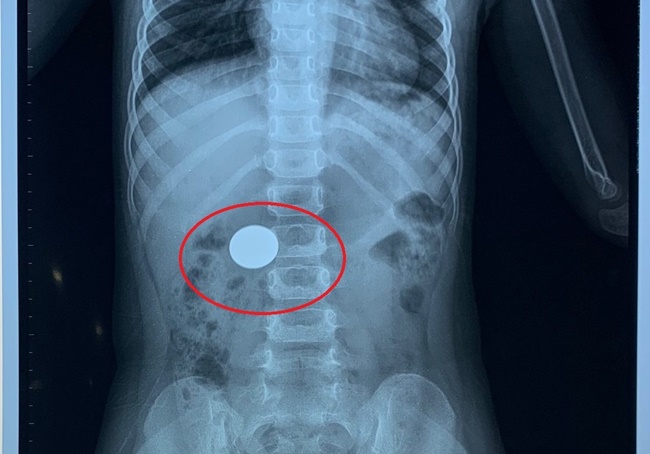

Hình ảnh chụp Xquang cho thấy đồng xu trong dạ dày. (Ảnh: BV) |

Bệnh viện Hoàn Mỹ Đà Nẵng vừa cứu thành công bé gái V.A.Y.N (4 tuổi) nuốt đồng xu trong lúc chơi đùa.

Chị L.T.M (mẹ cháu bé) cho biết, tối 13/12, khi đang chơi thì nghe cháu N. khóc. Gặng hỏi gia đình biết được cháu nuốt phải đồng xu. Thời điểm này bé vẫn ăn uống bình thường, không nôn ói.

Lo lắng, chị M. đưa con đi khám thì phát hiện có đồng xu trong dạ dày bé N,.

Tại bệnh viện, các bác sĩ hội chẩn, tiến tới chỉ định nội soi can thiệp thực quản dạ dày để gặp dị vật kịp thời, tránh những biến chứng không mong muốn có thể xảy ra cho cháu.

Sau 30 phút, tiến hành nội soi can thiệp các bác sĩ gắp ra ngoài một đồng xu kim loại, đường kính 2 cm.

Bác sĩ khuyến cáo bố mẹ nên cẩn trọng trong việc cân nhắc đồ chơi nào có thể cho con trẻ chơi, đặc biệt là với trẻ còn nhỏ tuổi. Nếu phát hiện con nuốt phải dị vật, bố mẹ cần đưa ngay đến các cơ sở y tế để thăm khám và xử trí kịp thời.

Tuyệt đối không được tự ý xử trí tại nhà bằng các mẹo dân gian, hoặc tự theo dõi để tránh tình trạng dị vật xuống ống tiêu hóa gây thủng hoặc tắc ruột, lúc này việc cứu chữa sẽ cực kì khó khăn.